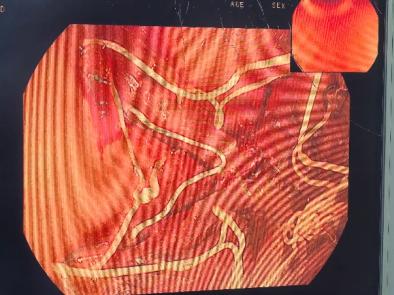

接诊后,胃肠及肝胆外科副主任王若谷详细为杨女士介绍了各种减重方式。经过综合评估,杨女士对胃转流支架治疗比较感兴趣。王若谷详细介绍了该技术的相关情况:胃转流支架是一种新兴的微创减重技术,通过在胃肠道内放置支架,改变食物的消化和吸收路径,从而达到减重的效果。听完介绍后,杨女士决定尝试这种新的治疗方法。

王若谷与内分泌与老年病科、营养科等科室专家,为杨女士制定了个性化治疗方案,提供全方位的治疗支持。入院第2天,王若谷带领团队在麻醉手术科、消化内镜中心等多科室协作下成功完成胃镜下胃转流支架植入,整个过程耗时不到半小时,术后杨女士无明显不良反应,术后第二天顺利出院。

胃转流支架手术是一种先进的微创介入技术,主要用于治疗肥胖症及相关代谢性疾病。通过内镜将一枚“记忆合金支架”精准植入十二指肠起始段,如同在消化道上游架起一座“临时立交桥”,使食物绕过十二指肠和部分空肠,直接进入中段肠道。这一过程可减少营养吸收、调节肠道激素,实现“减重+控糖”。